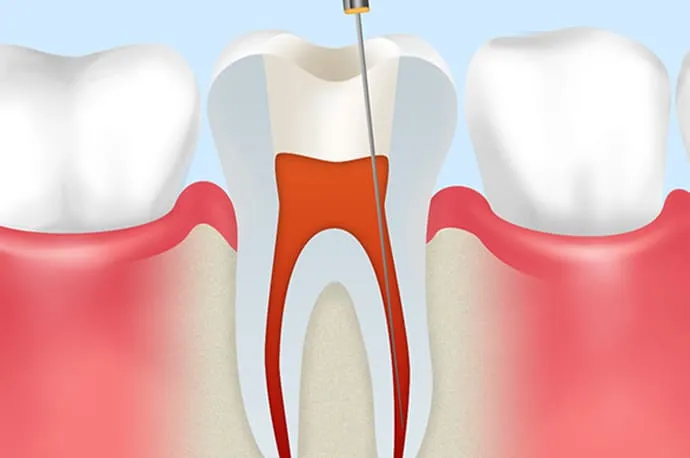

STEP 03

根管の長さの測定

根管口が見つかったら、ファイルと呼ばれる細い針金のような器具を根の先まで挿入し、根管の正確な長さを測定します。この工程が、治療の精度を左右する重要なポイントになります。

STEP 04

根管の清掃・消毒

測定した長さに合わせて、柔軟性のあるニッケルチタンファイルで根管を最小限に広げます。同時に消毒剤を使用し、根管内部を徹底的に洗浄・消毒していきます。